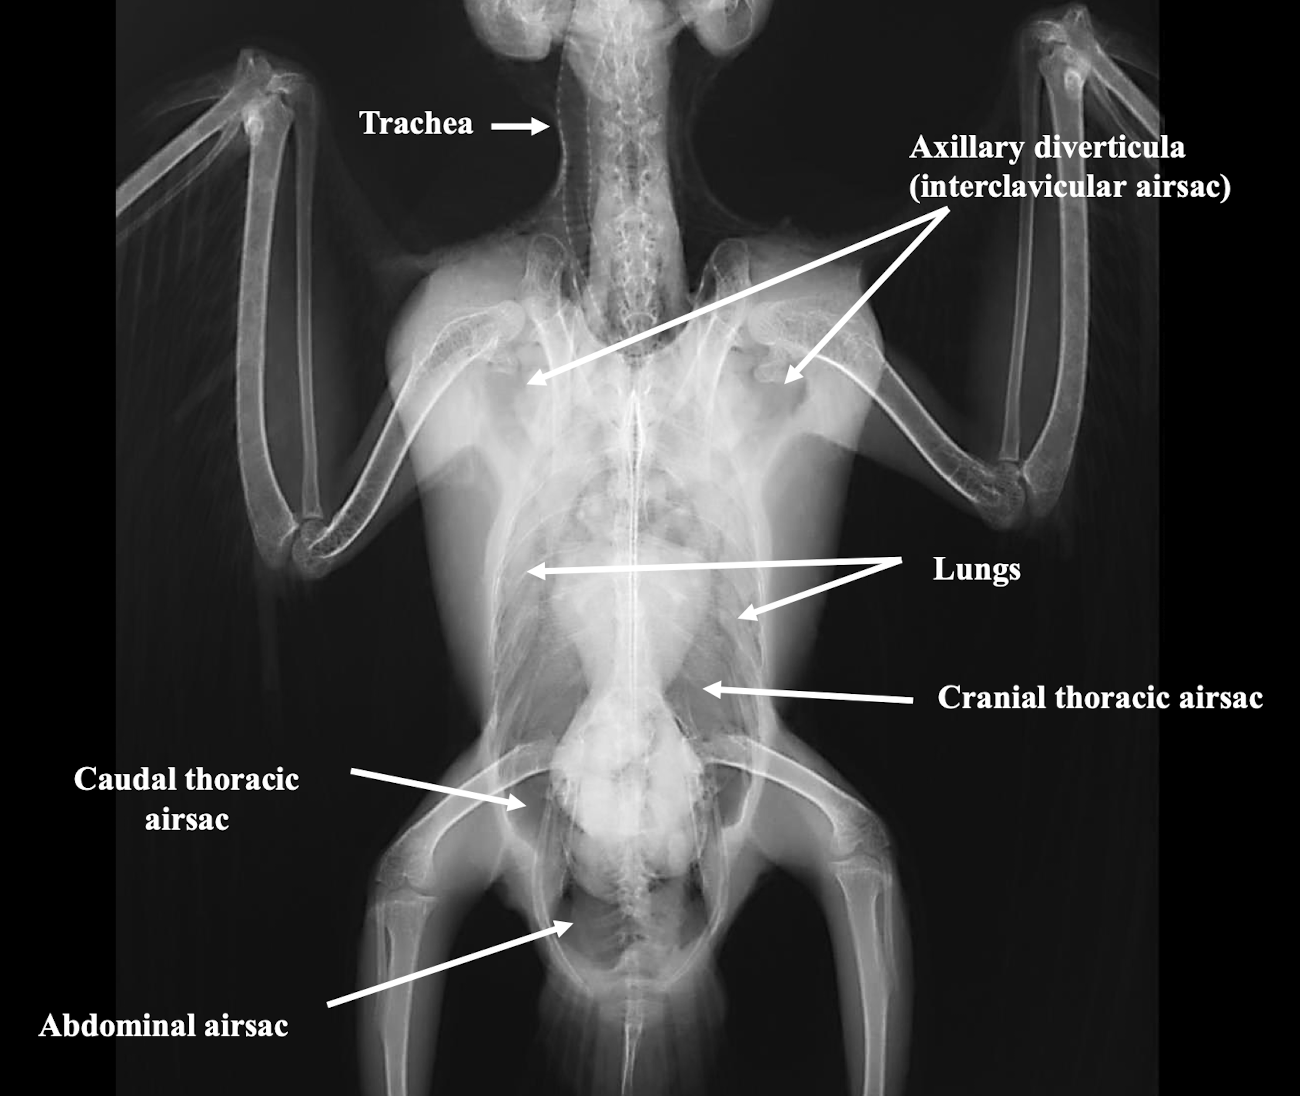

Which major air sacs are typically identified in avian respiratory imaging?

Interclavicular, cranial thoracic, caudal thoracic, and abdominal airsacs.